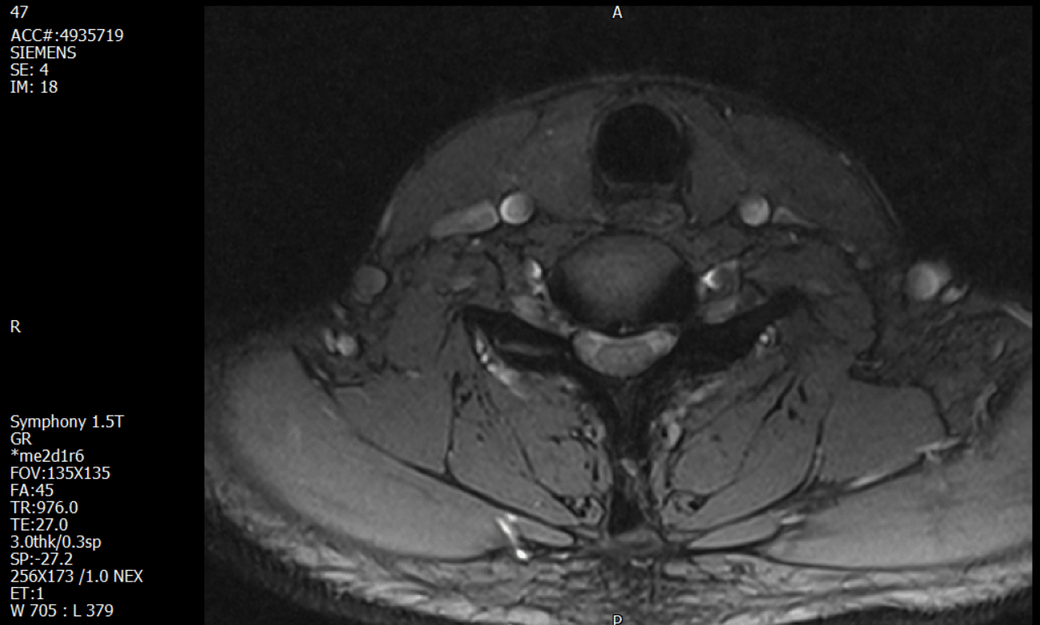

경추 요추 디스크 MRI판독 부탁드립니다.

- 3개월전 좌측 상지 저림(힘빠짐) 발생. 이틀뒤 에 좌측 하지 저림(힘빠짐) 발생.

-11월, 증상발생 직후 잠실소재 척추전문병원 MRI 요추경추 촬영 후 신경외과 박사 진료, 허리는 매우 건강, 경추는 퇴행성 진행되고 있지만 디스크라고 보기 어려움. 신경막만 살짝 건드리는 정도고 이 정도로 힘빠짐이나 저림이 오지 않고 원인은 다른 곳에 있을 가능성.

1. MRI 상 , 경추와 요추에 디스크가 있나요? 있다면 좌측 팔과 다리에 저림 및 힘빠짐을 줄 정도인가요?

• 2번 째 사진

• 1. MRI 사진을 보았을 때 디스크를 의심해볼 수 있는 소견이 살짝살짝 보이긴 합니다만, 상하지의 저림 및 힘빠짐을 유발할 정도인지는 솔직히 회의적입니다.

4. 말씀하신 것처럼 특히 요추부 MRI는 디스크를 찾기 어렵습니다.